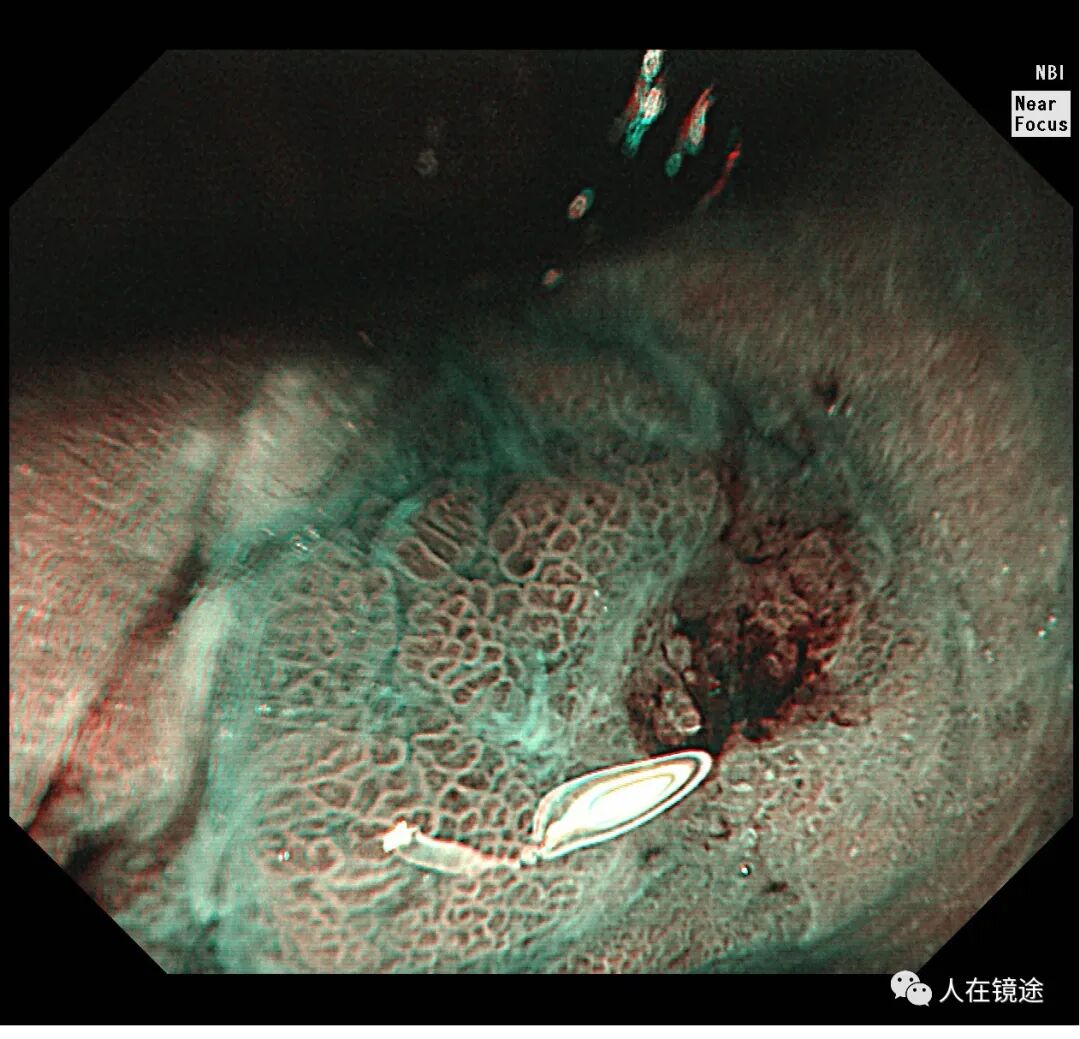

NBI+近焦示:胃窦小弯见一0.8*1.2cmIIa粘膜发病变呈咖色,边界清楚,微结构紊乱,表面粘膜高低不平伴自发性出血